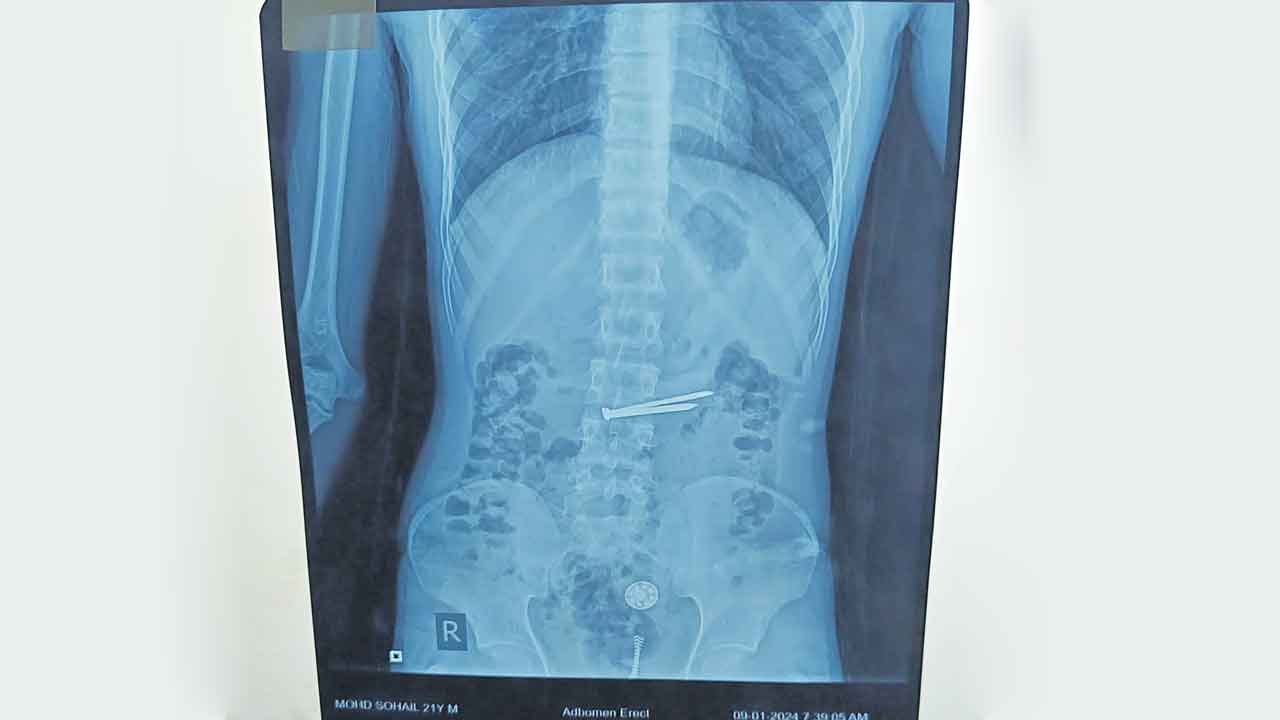

జనరల్ సర్జరీ విభాగం యూనిట్-7 ప్రొఫెసర్ డాక్టర్ బొంగు రమేశ్ రోగిని పర్యవేక్షించి మెడికల్ గ్యాస్ట్రో ఎంట్రాలజీ విభాగానికి రిఫర్ చేశారు. గ్యాస్ట్రో ఎంట్రాలజీ విభాగం హెచ్ఓడీ ప్రొఫెసర్ డాక్టర్ బి.రమేశ్ కుమార్ రోగికి ఎక్స్రే తీయించగా కడుపులో మేకులు, గోర్లు, ప్లాస్టిక్ వస్తువులు, మెటల్ ఉన్నట్లు గుర్తించారు. సుమారు గంట పాటు శ్రమించి ఎండోస్కోపి సహాయంతో వాటిని తొలగించారు. ప్రస్తుతం రోగి పూర్తిగా కోలుకొని ఆరోగ్యం ఉన్నట్లు వైద్యులు తెలిపారు.